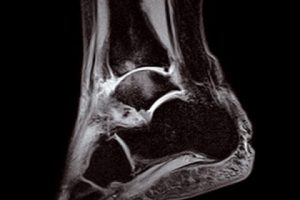

When you need high-quality extremity MRI, the O-scan dedicated MRI system is the perfect fit. The O-scan system’s complete range of extremity imaging capabilities, intuitive operation, and compact footprint combine to provide the optimal solution for both patients and practices.